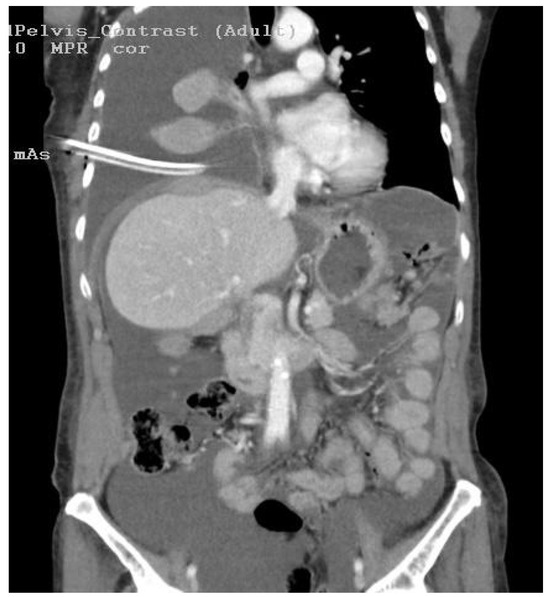

Successful Implementation of HITOC and HIPEC in the Management of Advanced Ovarian Carcinoma with Pleural and Peritoneal Carcinomatosis

Moldovan, B.; Saon, C.T.; Adam, I.-I.; Pisica, R.-M.; Silaghi, V.T.; Untaru, V.; Stoica, D.; Crisan, M.; Popianas, A.; Pescaru, F.; et al. Successful Implementation of HITOC and HIPEC in the Management of Advanced Ovarian Carcinoma with Pleural and Peritoneal Carcinomatosis. Diagnostics 2024, 14, 455. https://doi.org/10.3390/diagnostics14050455